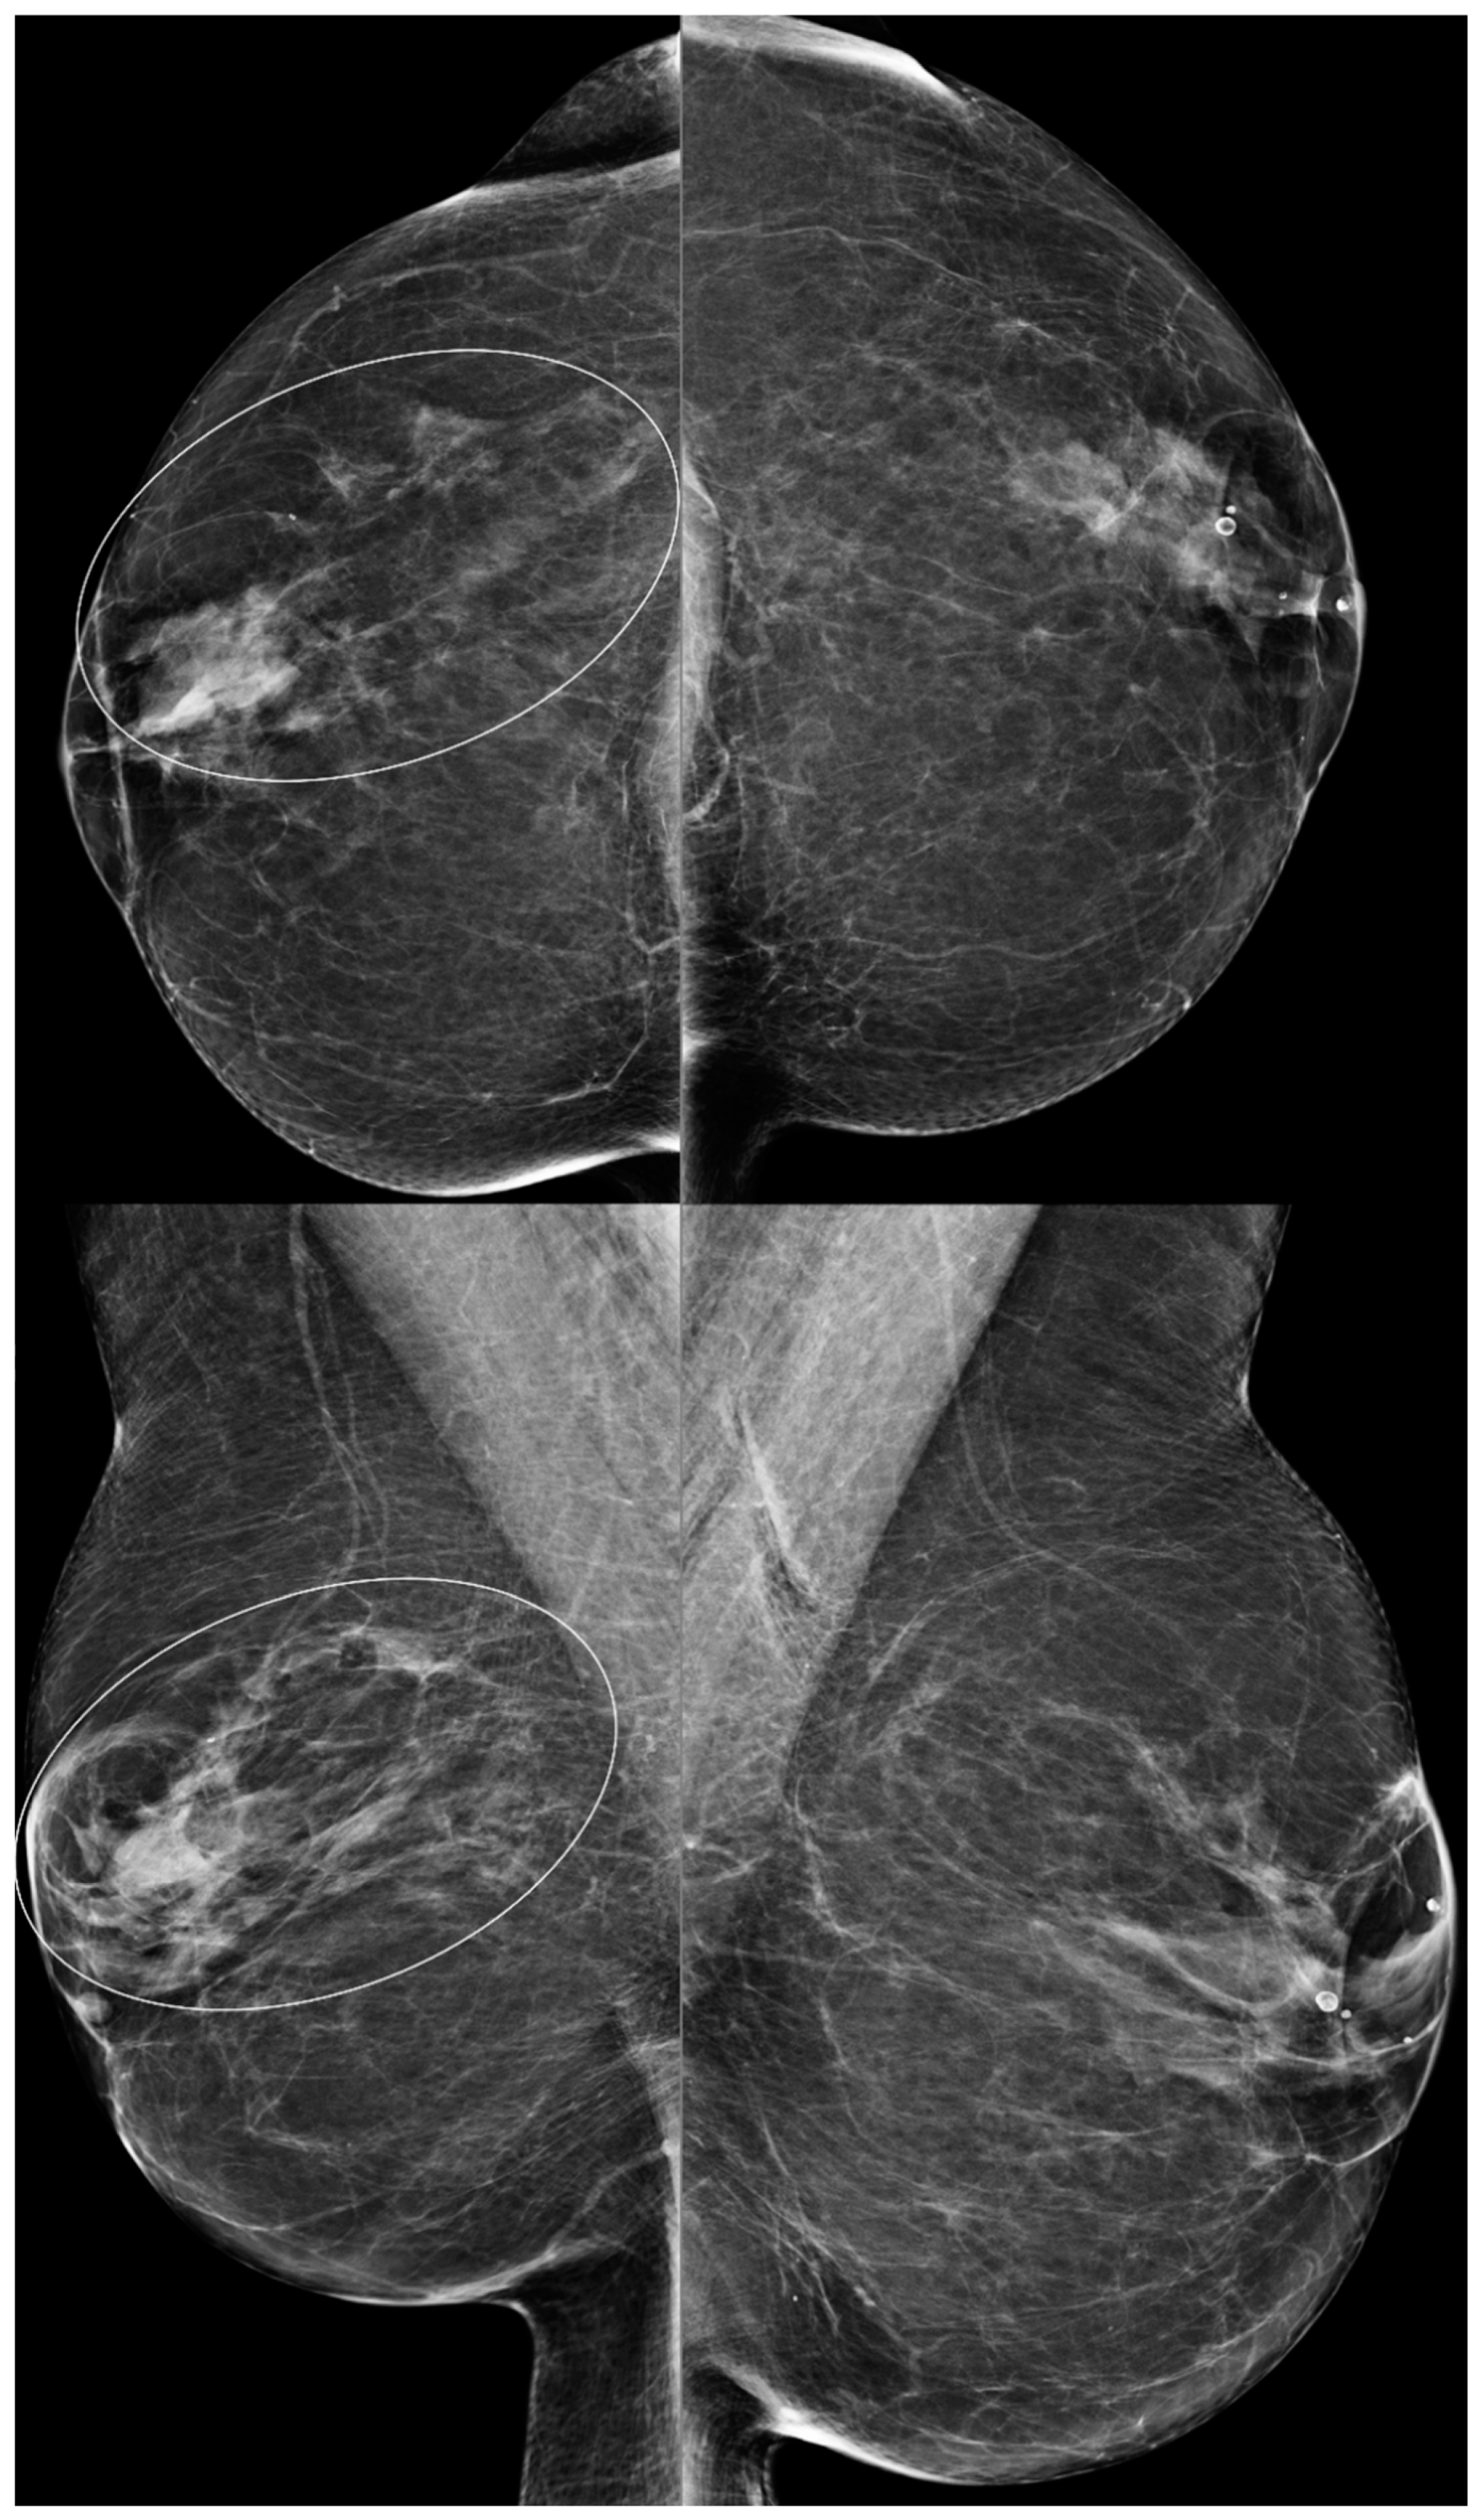

Suspicious findings in patients with a history of BES need to be thoroughly evaluated. Comparison examinations can be helpful. Silicone granulomas may distract the radiologist’s attention away from findings suspicious for breast cancer (Figure 14). Silicone granulomas may obscure important findings (Figure 15). Developing masses are suspicious and require further evaluation (Figure 16 and Figure 17).

Figure 16. A 52-year-old woman with a history of subglandular silicone implants. Prior mammograms with implant displaced views were negative. A screening mammogram with bilateral CC and MLO views one year after BES (a) demonstrates a spiculated mass in the left lower inner quadrant (arrow), which was biopsied under ultrasound guidance with pathology revealing invasive ductal carcinoma. T1-weighted post-contrast MRI axial images demonstrate areas of fat necrosis in both breasts ((b,c), arrowheads). An enhancing mass with a biopsy clip is seen adjacent to the surgical scar ((c), arrow) in the left breast representing the biopsy proven carcinoma.